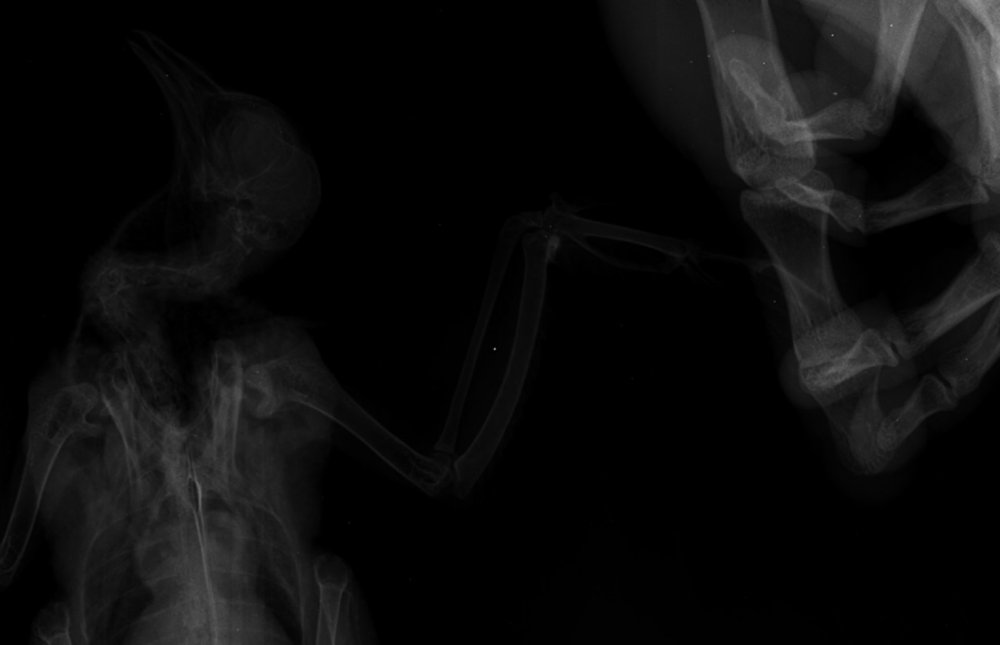

Duch Опубликовано 30 марта, 2020 #1 Опубликовано 30 марта, 2020 Здравствуйте! Приютился у нашего офиса, примерно 2 месяца назад, голубь и никак не улетал. Сделали вывод, что проблемы с крылом, т.к. левое он странно прижимал к себе. Положили в коробку, налили воды, насыпали гречи. Отогрелся спустя неделю, но крыло так и прижимал к себе. Предположили перелом крыла. Отвезли к орнитологу, сделали снимок (прикрепили к топику). Общий осмотр весьма позитивен, на снимке перелома нет. Выписали уколы витаминов и обезболивающих. Прокололи курс недели 2 назад - без изменений. На данный момент крыло так и прижимает к себе, огрызается, когда ему сыпят корм или доливают воды. Иногда клюёт и бьёт крылом, но только правым. Пока ждём выхода орнитолога из очередного отпуска, стараемся за ним ухаживать. В прошлую пятницу насыпали ему корм и подлили воды в плошку. Приехал в субботу вечером, дабы проведать. В итоге, он за целый день ничего не съел и не пил. На мои касания никак не реагировал: вжался в себя и стоял напуганный. Взял на руки, дабы осмотреть, как из под него показалась муха/слепень и тут же скрылась. Погуглил - оказывается, это - кровососки. Купил в ветеринарном отделе ампулу с препаратом, которую следовало разбавить 1,6л воды. Опрыскал её под крыльями, напоил водой из шприца и оставил так на день. Судя по корму, начал немного есть и пить. Кормплю гречкой, рисом и разваренным пшеном из шприца. Но сегодня обратил внимание, что он, когда клюёт сухой корм, как бы, промахивается и не может заглотить крупинку - гречка отскакивает в сторону и пытается еще раз захватить другую, но результат тот же. При всем при это, он четко видит мою руку и реагирует на неё соответствующим образом, т.е. слепоты нет Очень рассчитываю на вашу помощь! Ранее не имел опыта ухода за птицами

маленький принц Опубликовано 1 апреля, 2020 #5 Опубликовано 1 апреля, 2020 (изменено) а можно рентген более крупный а не мелкий? у Вас на этой мелкой картинке трудно разглядеть подробности ВНОВЬ ЛЕТАТЬ и Здоровья Вашему голубю! чтобы узнавать новые ответы в Вашей теме нажмите пожалуйста наверху Вашей темы "подписаться" Изменено 1 апреля, 2020 пользователем маленький принц

Duch Опубликовано 1 апреля, 2020 Автор #6 Опубликовано 1 апреля, 2020 31.03.2020 в 01:36, Виктория М. сказал: Здравствуйте. Нужен точный вес голубя. Помет желательно на листе белой бумаги. Проверьте нет ли наростов во рту , а также неприятныого запаха (кислого, тухлого). Кормить; 1 столовая ложка с горочкой 2 раза в день. Помимо гречи добавьте перловую крупу ,чечевицу или колотый горошек, пшеницу, овес без шелухи. Рис лучше уберите его можно но совсем немного. С каким препаратом ампула была? Все что обнаружил врач и все его назначения нужно выложить сюда на сайт, чтобы понимать чем вы лечили птицу. Какие витамины кололи какой курс и тд. Чтобы голубь начал нормально клевать зерно, в человеческой аптеке купите ноотропил таб или пирацетам . В вет аптеке нужно приобрести Фоспренил. Мух кровососок если вдруг еще обнаружите хорошо в тазике с водой вылавливать. Сажаете птицу в тазик с теплой водой, чтобы только голова на поверхности была, придерживаете аккуратно и так мин 10 -15 сидите с ним они начнут всплывать. Ваша задача не дать им вылететь из воды - передавить. Какое крыло он прижимает если смотреть на ренген? Прикрепил назначение врача Во рту ничего подозрительного, как и в запахе. Может прозвучать неоднозначно, но он в вцелом, приятно пахнет) Ампула, которую разбавил в воде и опрыскивал 2 дня голубя под перья ( на тело) - "Дельцид" В воду окунали, правда держали минут 5. Ничего не всплыло и мы аккуратно его сушили феном, т.к. он сильно замёрз. Потом на форуме прочел, что насильное купание голубей недопустимо Глядя на рентген то, что раскрыто, т.е. правое. Делали снимок лёжа на спине, соответственно, по факту, это левое крыло

OFA Опубликовано 2 апреля, 2020 #25 Опубликовано 2 апреля, 2020 @Duch сама доктор смотрела рентген птицы? Что-то сказала? Нужно позвать нашего форумского доктора @Zosia посмотреть рентген. Может так разложена птица, но мне что-то кажется, что плечевой сустав не в порядке, но лучше пусть Зося посмотрит. Птица взрослая, клевать умеет, значит проблема или с жкт, или вертячка в такой форме.

маленький принц Опубликовано 2 апреля, 2020 #26 Опубликовано 2 апреля, 2020 @OFA рентген - в виде мелкой картинки просил автора залить рентген покрупнее

маленький принц Опубликовано 2 апреля, 2020 #30 Опубликовано 2 апреля, 2020 (изменено) @Duch вот рентген Вашего пациента Изменено 2 апреля, 2020 пользователем маленький принц

маленький принц Опубликовано 3 апреля, 2020 #33 Опубликовано 3 апреля, 2020 12 часов назад, Duch сказал: ну да, разве не его я прикрепил в прошлом сообщении? оно почему-то ужалось до мелких размеров если пойти по ссылке https://www.mybirds.ru/forums/uploads/monthly_2020_03/1SXcxYu_0rk.jpg.d7c82758490ddb04a65127b887286e57.jpg.28c0e1b9697a84b0cce71b1ee39e8254.jpg и открыть то видно что оно очень мелкое потому я скачав Ваш архив перезалил фото и увидев что оно ограничено по размерам дважды обрезав перезалил ещё раз